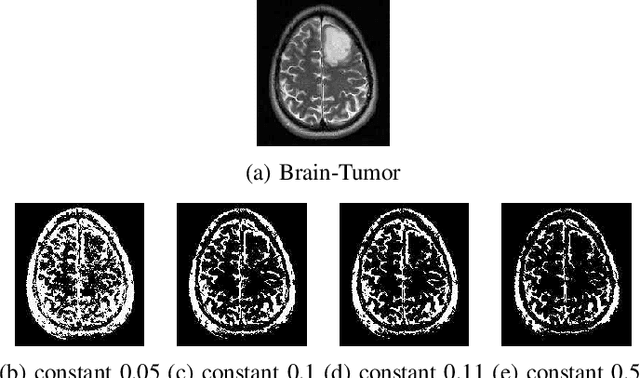

Abstract:Image segmentation refers to the separation of objects from the background, and has been one of the most challenging aspects of digital image processing. Practically it is impossible to design a segmentation algorithm which has 100% accuracy, and therefore numerous segmentation techniques have been proposed in the literature, each with certain limitations. In this paper, a novel Falling-Ball algorithm is presented, which is a region-based segmentation algorithm, and an alternative to watershed transform (based on waterfall model). The proposed algorithm detects the catchment basins by assuming that a ball falling from hilly terrains will stop in a catchment basin. Once catchment basins are identified, the association of each pixel with one of the catchment basin is obtained using multi-criterion fuzzy logic. Edges are constructed by dividing image into different catchment basins with the help of a membership function. Finally closed contour algorithm is applied to find closed regions and objects within closed regions are segmented using intensity information. The performance of the proposed algorithm is evaluated both objectively as well as subjectively. Simulation results show that the proposed algorithms gives superior performance over conventional Sobel edge detection methods and the watershed segmentation algorithm. For comparative analysis, various comparison methods are used for demonstrating the superiority of proposed methods over existing segmentation methods.